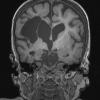

Hypoxia-Ischemia, fetal-neonatal

Porencephaly (4)